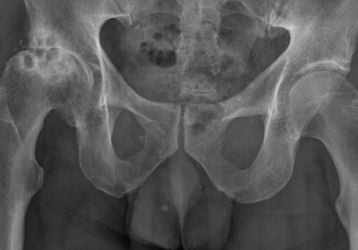

Гимнастика при коксартрозе: польза, результаты, противопоказания

Гимнастика при коксартрозе тазобедренного сустава и основные правила ее проведения. Наиболее эффективные упражнения и основные противопоказания к их проведению

Самые эффективные упражнения при коксартрозе тазобедренного сустава

Какие упражнения при коксартрозе тазобедренного сустава следует выполнять при легой стадии и при тяжелой. Комплекс упражнений по Бубновскому и Евдакименко.